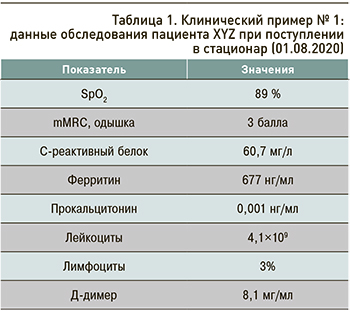

Данные обследования пациента при поступлении отражены в таблице 1.

На картине КТ грудной клетки – классические признаки коронавирусной инфекции (рис. 1).

Данные обследования пациента на 11.08.2020 приведены в таблице 2.

Тест ПЦР на SARS-CoV-2 от 10.08.2020 отрицательный.

На контрольной мультиспиральной КТ сохранялись остаточные изменения легочной ткани, соответствующие поражению при COVID-19, КТ-3.